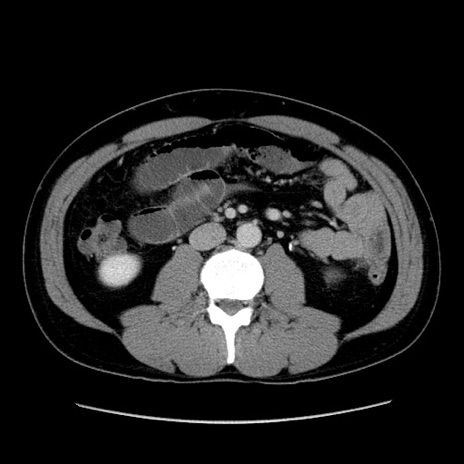

症例4(横断像)

【症例】30歳代男性

【主訴】腹痛、嘔吐

【現病歴】昨晩から突然の腹痛あり、その後嘔吐、軟便も出現。腹痛が改善しないため救急搬送となる。2日前にしめ鯖の食事歴あり。

【身体所見】意識清明、苦悶様、BP 135/90mmHg、BT 35.7℃、腹部:平坦、やや硬、心窩部〜臍部に自発痛、圧痛あり、筋性防御+、反跳痛-

【データ】WBC 8100、CRP 0.57